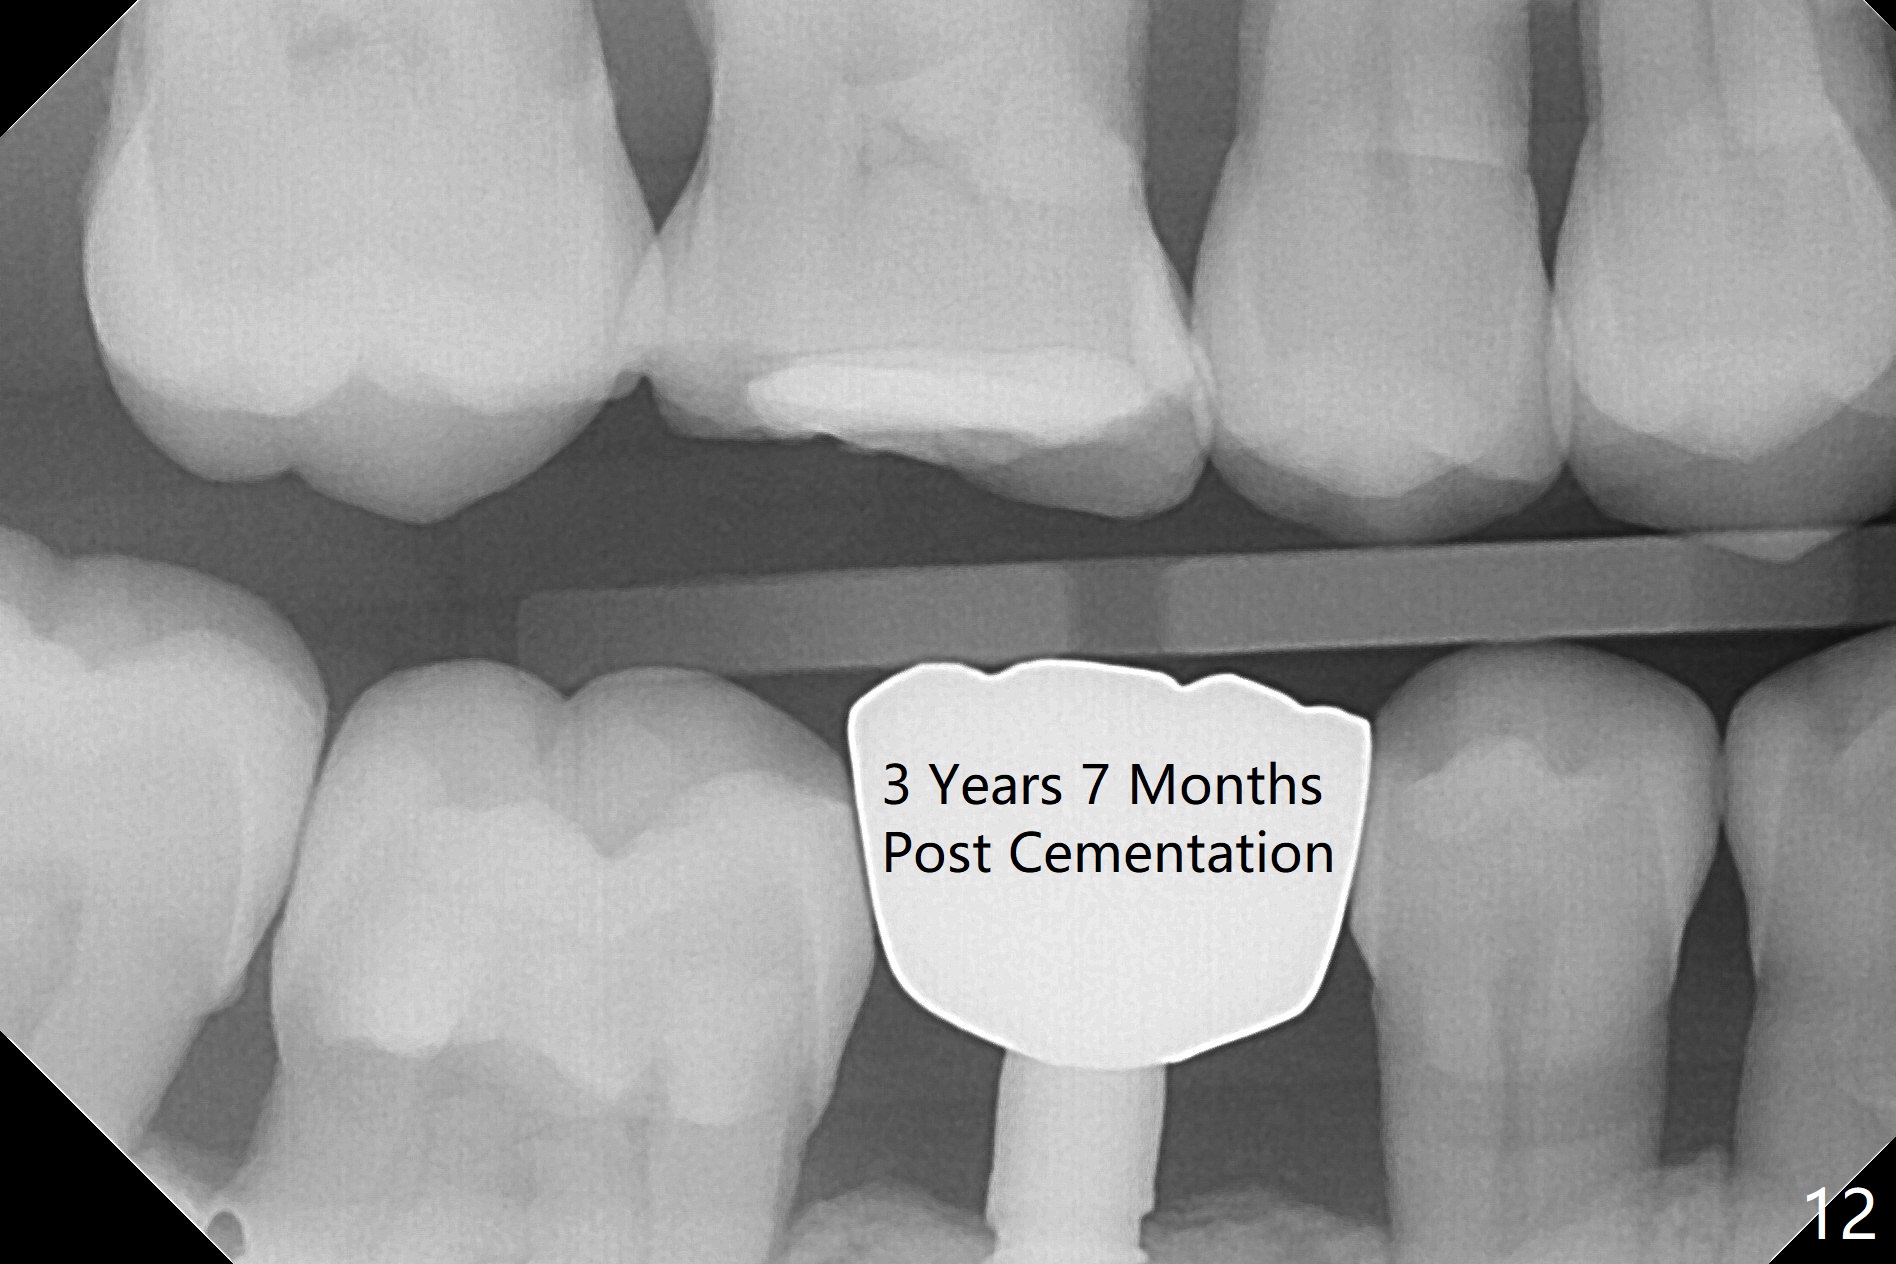

Before crown cementation, the ridge looks wider (Fig.7 *) than preop. There is no diastema between #31 and 32 (Fig.8, 17 days post cementation). The patient is pleased with less food impaction. The total treatment (including ortho) is 16 months. It appears that distalization of #29 is not effective to gain the bone width. In fact simultaneous GBR with implant placement is much more efficient. There is no bone loss 3 months post cementation (Fig.9). The gingiva looks healthy 10 months post cementation (Fig.10). The implant crown is functioning 1 year 9 months post cementation (Fig.11) and 3 years 7 months post cementation (Fig.12).